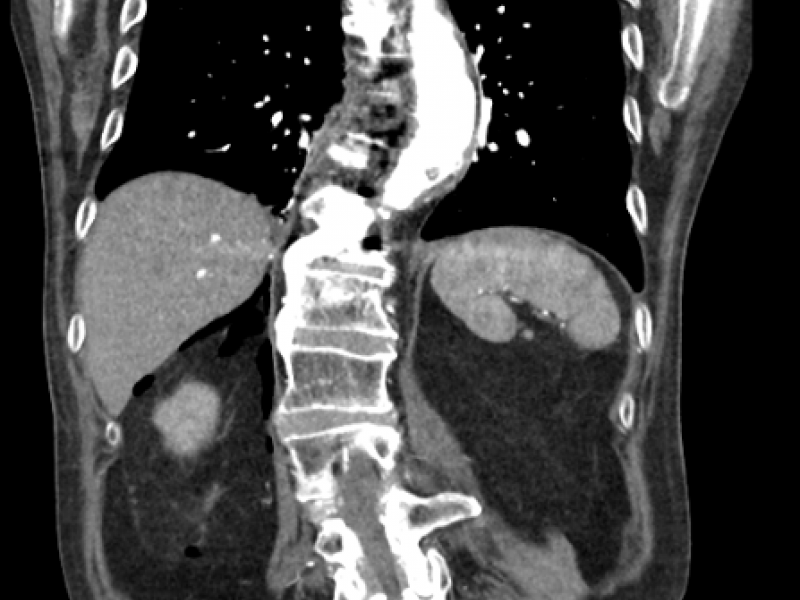

A 70 yo M presents to the ED with back pain s/p fall one day